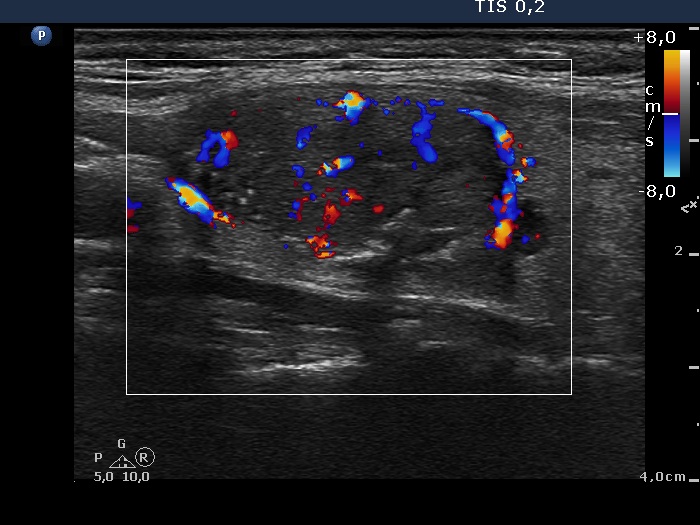

The borders of the nodule - case 2081 (ultrasonographic picture 4)

Right lobe, longitudinal scan, color Doppler mode.